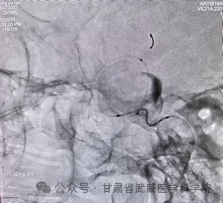

术中释放密网支架

术中弹簧圈疏松填塞